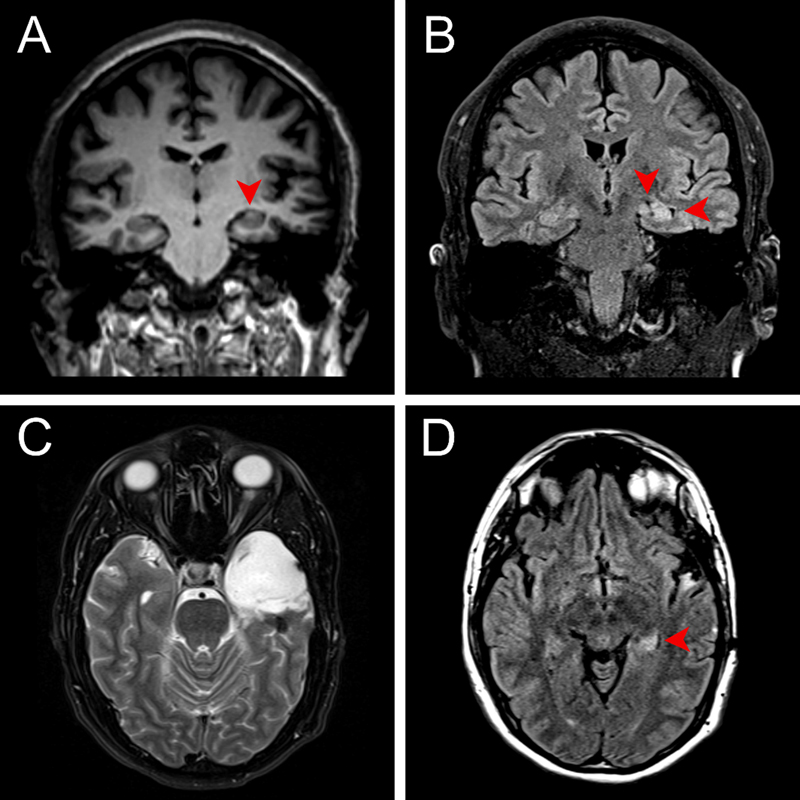

A 31-year-old right-handed male with a five-year history of focal epilepsy refractory to medical management presented to the Comprehensive Epilepsy Center for advanced monitoring and surgical planning. The patient’s seizures developed shortly after undergoing surgery for the removal of a bone spur that was complicated by a deep vein thrombosis requiring anticoagulation. The initial semiology included focal seizures with impaired awareness and generalized tonic-clonic (GTC) seizures with rightward head turn. Although the GTC seizures were controlled with valproic acid and lacosamide, he continued to have focal seizures without impaired awareness and failed a trial of levetiracetam. These seizures began with a sensation of déjà vu, followed by hyperventilation and oral automatisms. Magnetic resonance imaging (MRI) showed left hippocampal hyperintensity and mild volume loss, consistent with left mesial temporal lobe sclerosis, without evidence of mass lesion (Figure 1). After two unsuccessful attempts at electrographically characterizing seizures with noninvasive EEG, the patient underwent stereoelectroencephalography (sEEG) implantation, which localized the seizures to the left temporal lobe. A Wada test demonstrated the dominance of the left hemisphere for language and the right for memory. The case was discussed at the multidisciplinary epilepsy clinic, and after patient consent was obtained for surgery and involvement in research, he underwent left craniotomy for temporal lobectomy and amygdalohippocampectomy. The procedure was uncomplicated, and the patient went home on postoperative day 1. A neuropsychological evaluation performed 11 months after surgery showed improvement in measures of verbal memory and a cognitive profile essentially within normal limits. Two years after surgery, the patient has had occasional episodes of dysmnesic phenomena (déjà vu auras) but has not had any seizures, corresponding to Engel class IB (Supplementary Figure 1).

Figure 1. Preoperative coronal MRI at the level of the hippocampal body (A) T1 MP-RAGE demonstrating left hippocampal atrophy and architectural distortion, and (B) T2/FLAIR showing abnormal hyperintense signal with atrophy and associated widening of the temporal horn (right arrowhead) and choroid fissure (left arrowhead). Postoperative axial T2 (C) MRI at the level of the pons demonstrating postoperative changes following left anterior temporal lobectomy and (D) T2/FLAIR at the level of the mesencephalon showing abnormal hyperintense signal in the residual left hippocampal tail.